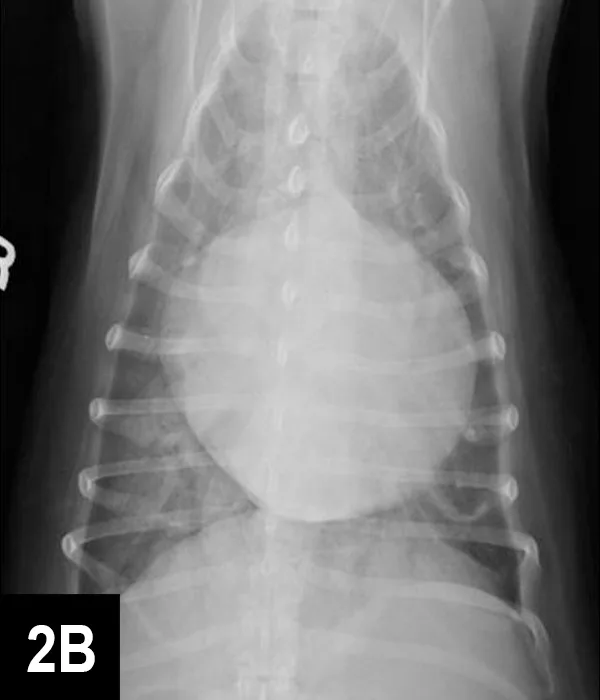

FIGURE 2B

VD thoracic radiograph

A sinus rhythm (HR is ~150 bpm) and left ventricular enlargement pattern were noted on ECG: the sensitivity was decreased to 5 mm/mV, and R waves measured ~3 mV (upper end of normal R-wave height is 2.5 mV). Thoracic radiographs revealed severe left atrial enlargement with moderate left ventricular enlargement. There was a moderate interstitial to alveolar pulmonary pattern most pronounced in the caudodorsal lung fields, which is consistent with left-sided congestive heart failure resulting from degenerative mitral valve disease.